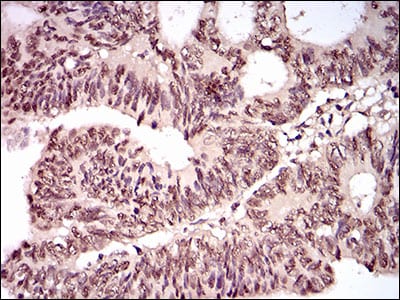

Immunohistochemical analysis of paraffin-embedded human bladder cancer tissues using TBLR1 mouse mAb with DAB staining.

Immunohistochemical analysis of paraffin-embedded human rectum cancer tissues using TBLR1 mouse mAb with DAB staining.